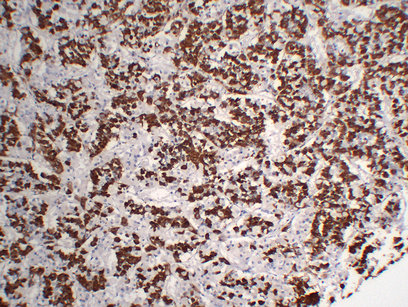

Immunohistochemistry analysis of paraffin-embedded Pituitary using Growth Hormone antibody.High-pressure and temperature Sodium Citrate pH 6.0 was used for antigen retrieval.